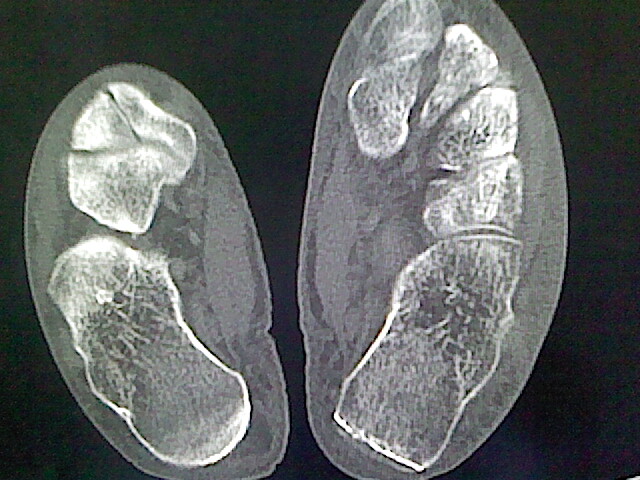

标题: CT16814:男,76岁,左小腿疼痛,不能站立 大家给看看 [打印本页]

男,76岁,左小腿疼痛,不能站立